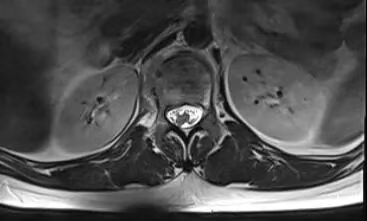

患者术前磁共振检查影像学表现:

患者术前的磁共振检查结果提示:L1椎体病变,结合病史考虑为转移癌。影像学评估提示L1椎体高信号表现,椎体高度未发生塌陷表现,椎管内容物无受压表现。患者临床腰椎功能活动受限,疼痛明显,相关生命体征平稳。